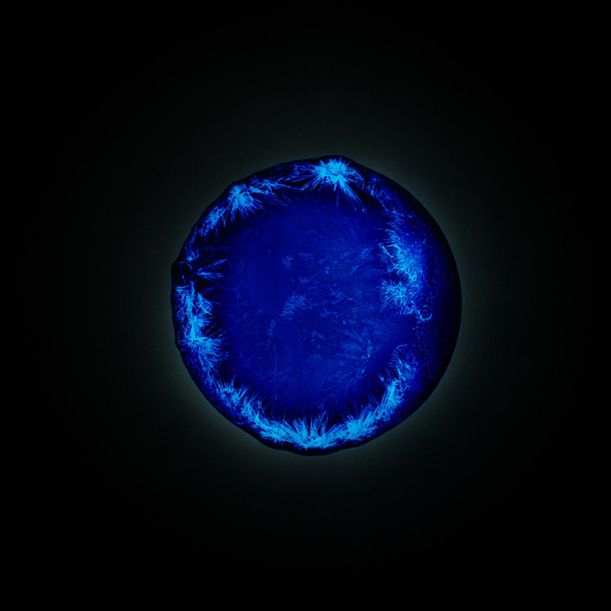

7. LSD

Dietylamid kyseliny lysergové neboli zkráceně LSD je asi nejznámější droga ze skupiny halucinogenů. Změna vnímání reality a určité odosobnění může být sice inspirativní, ale riskujete i tzv. badtrip – stav, při kterém se neuvolňuje dostatečná hladina serotoninu, takže vám pocity, které by vás za jiných okolností pobavily, připadají jako noční můra. Koledujete si i o duševní poruchu. Můžete zažít i tzv. flashback neboli po týdnu uprostřed pracovní schůzky najednou ‚cvak‘, a potácíte se znovu uprostřed halucinací.